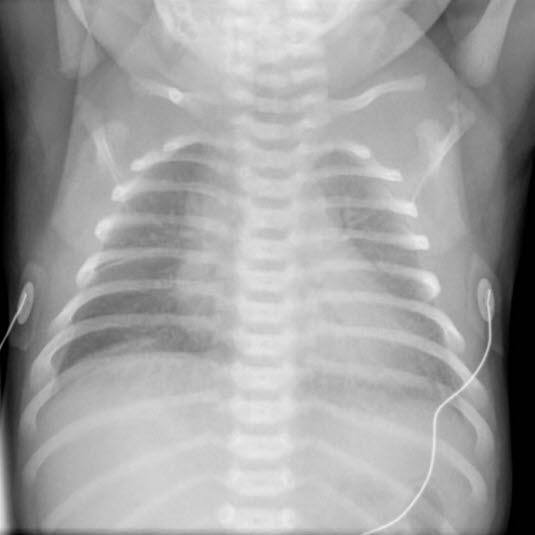

Røntgenbilde av lungene kan vise typiske forandringer.

Tilstanden mistenkes når det observeres grynting, inndragninger og andre typiske ubehagssymptomer hos for tidlig fødte barn like etter fødselen. Røntgenbilder kan vise typiske forandringer.

Mekoniumfarget fostervann forekommer ved ca. 15 prosent av fødslene og blant disse oppstår pustevansker hos 10-15 prosent - hyppigst blant barn født til termin eller etter termin2. Tilstanden gir betydelige pustevansker umiddelbart etter fødselen, og det observeres at fostervannet er misfarget. Røntgen av lungene kan også vise forandringer.

Tilstanden kan forløpe på ulike måter, men de mest fremtredende symptomene er pustebesvær og feber. Tilstanden utvikler seg over tid, slik at pustebesvær oppdages først timer til dager etter fødselen. Røntgen av lungene kan vise typiske forandringer. Det kan påvises bakterier i blodet.

Tidspunktet for fødselen i forhold til termin gir viktig informasjon om hvilken tilstand som kan foreligge. Eventuell avklaring av problemer som har oppstått under fødselen, kan også gi hint om underliggende årsak. Legeundersøkelsen er avgjørende. Andre undersøkelser som kan komme på tale, er røntgen av lungene, puls og oksygenmåling, blodprøver.